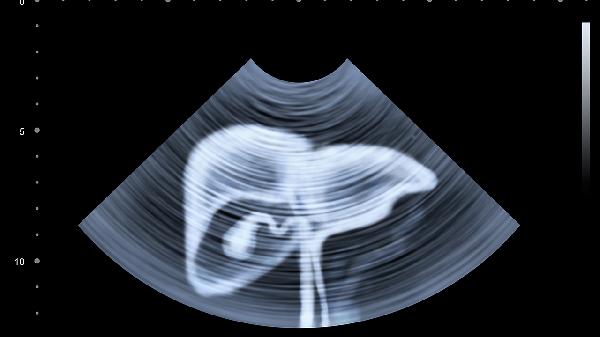

甲胎蛋白是一种糖蛋白,主要由胎儿肝细胞和卵黄囊合成,出生后水平迅速下降。成年人甲胎蛋白升高通常提示肝脏病变,轻度升高可见于慢性肝炎或肝硬化活动期,此时肝脏B超可能显示肝实质回声增粗、肝表面不平等非特异性改变。中度升高需警惕肝癌风险,肝脏B超能发现低回声结节、占位性病变等典型表现。部分非肝脏疾病如睾丸或卵巢生殖细胞肿瘤、妊娠期女性也可能出现甲胎蛋白升高,但这类情况通常伴有其他特异性临床表现。

极少数情况下,甲胎蛋白升高可能与检测误差或良性肝病相关,如急性肝炎恢复期可出现一过性升高。对于持续异常但B超未发现明确病变者,建议进一步行增强CT或核磁共振检查。某些遗传代谢性疾病如酪氨酸血症也会导致甲胎蛋白持续偏高,这类患者往往伴有生长发育迟缓等全身症状。